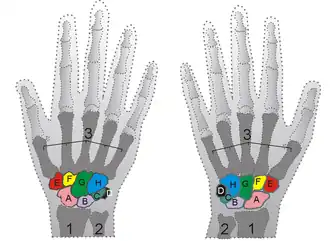

The scapholunate ligament is an intraarticular ligament binding the scaphoid and lunate bones of the wrist together. It is divided into three areas, dorsal, proximal and palmar, with the dorsal segment being the strongest part.[3] It is the main stabilizer of the scaphoid. In contrast to the scapholunate ligament, the lunotriquetral ligament is more prominent on the palmar side.